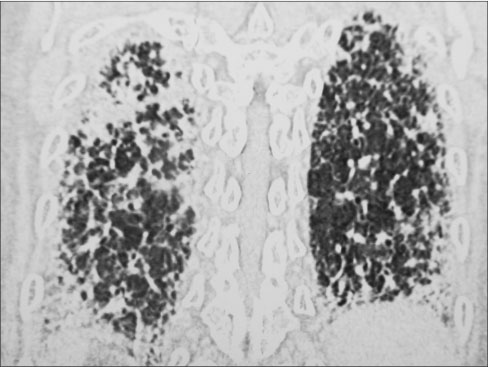

After seven cycles of chemotherapy, the patient presented with weakness, cough, and exertional dyspnea. On examination, the patient was dyspneic on rest and there were bilateral basal crackles in the chest. Initial blood gases were within normal limits. He was started on supportive care with broad-spectrum antibiotics, bronchodilators, and later antifungals. When there was no response to therapy, CT scan of the chest [Figure 4] and [5] and abdomen was done which showed extensive areas of intra- and interlobular septal thickening with fine reticulation in the bilateral lung parenchyma, particularly peripherally and basal. Abdominal films showed further improvement in liver lesions which were only subcentimeter in size. His blood and bronchial cultures were negative for any pathologic organisms. Despite aggressive supportive care, the patient expired after 2 weeks of admission.

| Figure 5 Post treatment computed tomography scan chest, lateral sagittal view